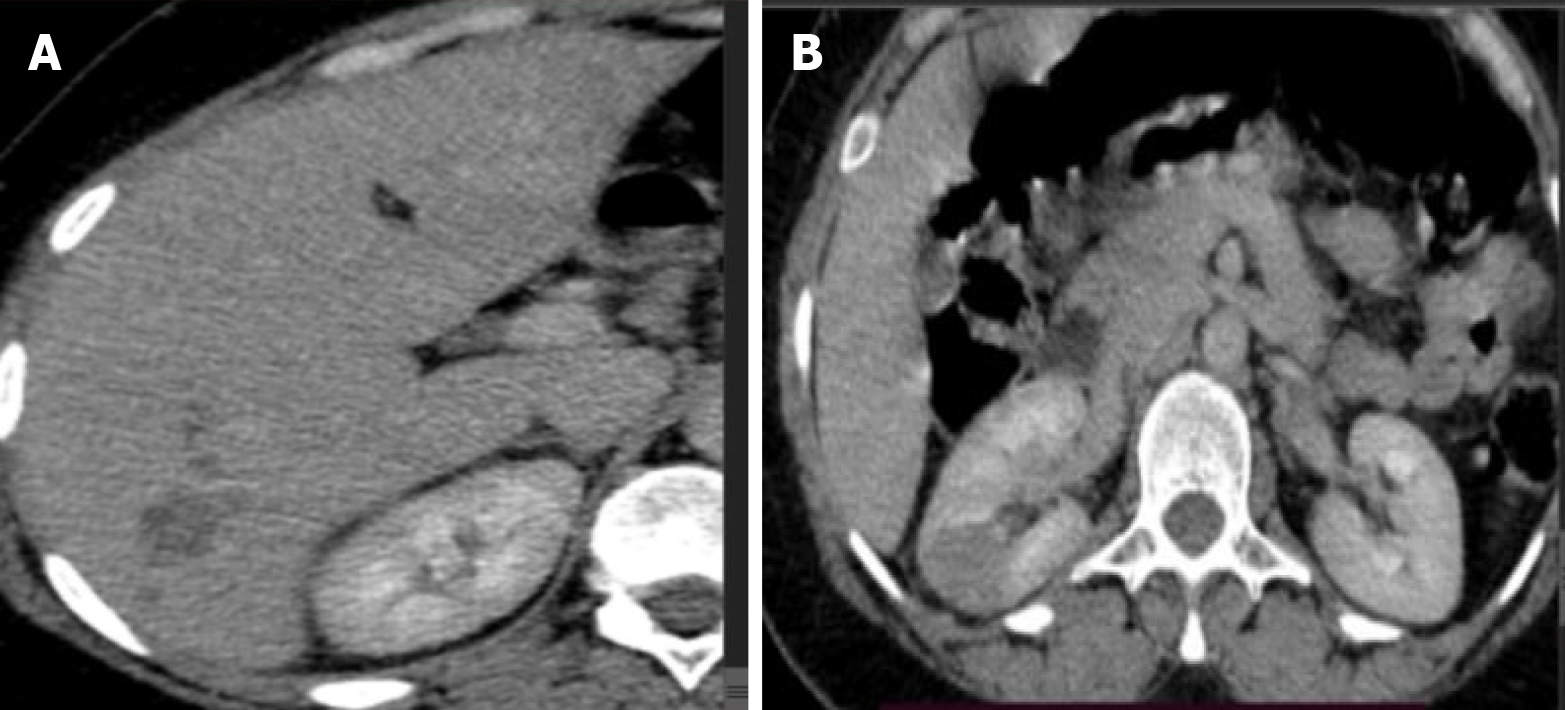

Figure 4 Abdominal computed tomography scan consistent with hepatic and kidney fasciola involvement.

A and B: The above computed tomography image showed hepatic segment 6 small subcapsular hypodense lesion with peripheral enhancement likely Fasciola hepatica (the hepatic lesions on segment 6 were clusters of oval hypodense nodules with peripheral enhancement where there is also mild biliary tree dilatation) (A). Multiple hyperdense lesions were also seen on both kidney’s (B).